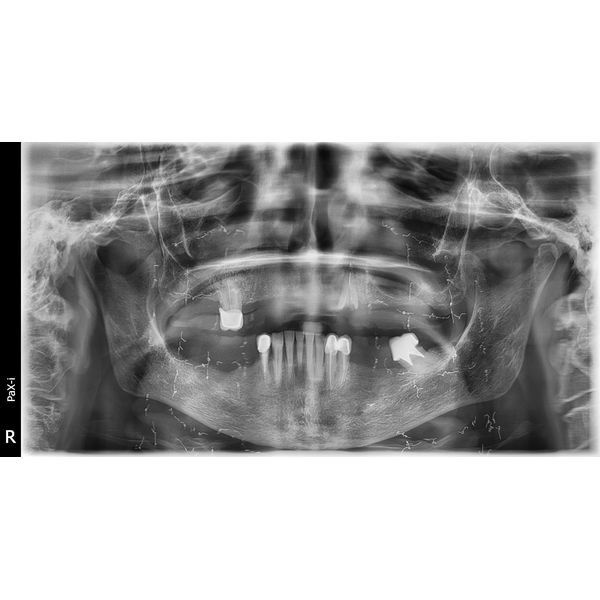

Компьютерная томография (КТ) верхней и нижней челюсти показала атрофию альвеолярного гребня (уменьшение объёма и высоты костной ткани челюсти) и опущение десны, из-за чего корни зубов были оголены. Воспалительных процессов в костной ткани не было, гайморовые пазухи оставались чистыми, височно-нижнечелюстной сустав в норме.

Пародонтоз 3 (тяжёлой) степени. Оголение корней зубов на две трети. Частичная вторичная адентия верхней и нижней челюсти. Хронический периодонтит верхнего правого и нижнего левого зуба.

Полгода женщина носила временную конструкцию. За это время она дважды делала контрольные ортопантомографические снимки и компьютерную томографию, чтобы контролировать состояние полости рта. Когда импланты прижились, ей поставили постоянный протез.